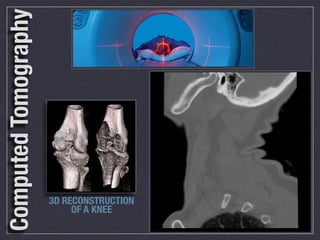

Computed Tomography

3D RECONSTRUCTION

OF A KNEE